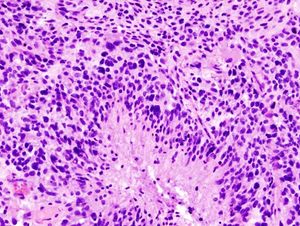

뇌종양 분류는 전통적으로 육안 수준에서 헤마톡실린-에오신 염색을 통해 측정한 조직 병리학을 기반으로 해왔다. 세계 보건 기구는 1979년에 첫 번째 표준 분류를 발표했으며[35], 그 이후로 계속해오고 있다. 2007년 세계 보건 기구의 중추신경계 종양 분류[36]는 주로 현미경적 특징을 기반으로 한 마지막 분류였다. 새로운 2016년 세계 보건 기구의 중추신경계 종양 분류[37]는 패러다임의 전환을 가져왔다: 일부 종양은 세포 형태뿐만 아니라 유전적 구성에 의해서도 정의되었다.

신경교 세포(주로 별아교 세포)에서 기원하는 악성 종양 중, 극도로 미분화되어 증식 능력이 높은 것을 교모세포종이라 한다. 종양은 출혈을 동반하는 경우가 많으며, 종양 내부에 괴사 덩어리가 관찰되기도 한다. 종양 세포는 원형, 방추형 등 다양한 형태를 가지며, 크기가 일정하지 않다.